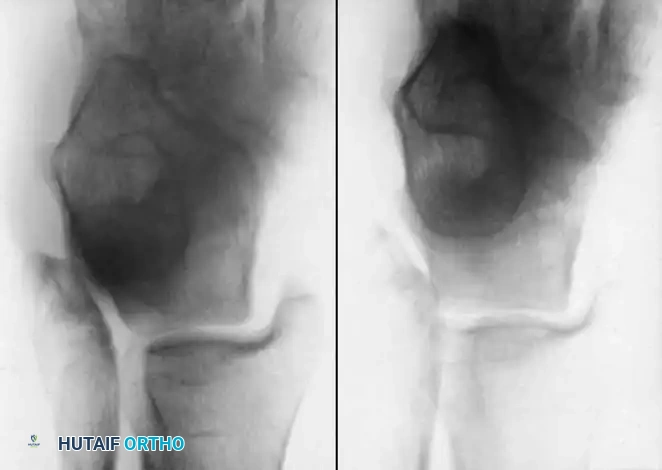

Inversion and Eversion Stress Tests (Talar Tilt)

Complete rupture of the deltoid ligament, including the deep portion, is rare in isolation. When the deltoid is completely ruptured in conjunction with a syndesmotic tear or lateral malleolus fracture, the talus shifts laterally with eversion stress.

If the lateral ligaments are completely disrupted, the talus tilts abnormally within the mortise under inversion stress. This stress is best applied with the ankle in slight plantarflexion to isolate the ATFL.

- Bonnin's Criteria: A talar tilt of 15 degrees indicates isolated ATFL rupture; 15 to 30 degrees indicates combined ATFL and CFL rupture; >30 degrees indicates rupture of all three lateral ligaments.

Meyer et al. warned that subtalar sprains frequently masquerade as ankle sprains. Negative stress radiographs in the presence of severe clinical instability should raise high suspicion for an underlying subtalar ligamentous disruption (e.g., interosseous talocalcaneal ligament).